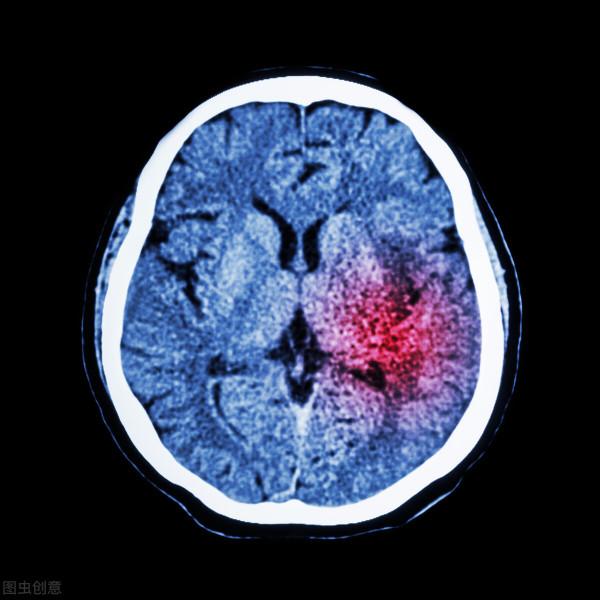

在這裡需要強調一個問題,腦梗死的人多,還是腦出血的人多呢?

其實在這些需要住院的患者當中,有81.9%是因為腦梗死需要住院,而腦出血患者僅為14.9%。

很多患者突然出現一側肢體沒有力量笨拙,感覺到非常麻木沉重,其實這都是腦卒中的常見表現。